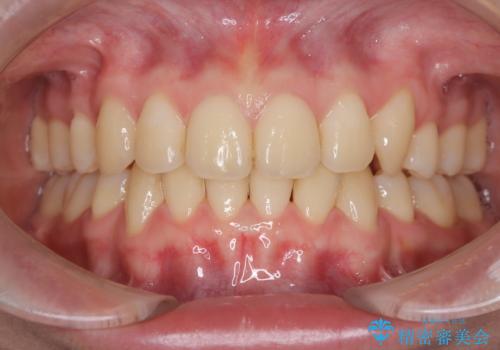

- 八重歯が気になるとのことでご相談いただきました。診察すると、歯列のスペース不足により犬歯が外側に飛び出している状態でした。このままでは歯を並べるスペースが足りないため、抜歯矯正が必要と判断。治療は目立ちにくいインビザラインで行い、歯の移動をサポートするためにゴムかけ(顎間ゴム)を併用する計画を立てました。

抜歯後、インビザラインを用いて少しずつ歯を移動させ、空いたスペースに八重歯を整列させました。さらに、ゴムかけを行うことで上下の噛み合わせを適切に調整。治療後は、八重歯が綺麗に並び、バランスの取れた歯並びと自然な噛み合わせを実現できました。患者様にも「仕上がりがとても綺麗で、口元の印象が変わった」とご満足いただきました。